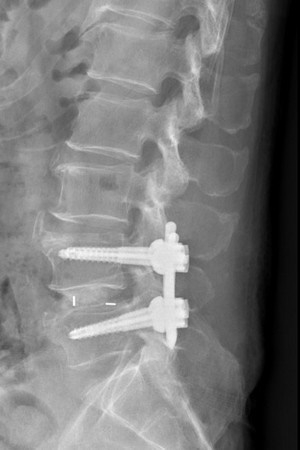

67歲的黃先生,去年務農時摔傷後又搬運重物,造成腰痛症狀不斷加劇,嚴重時甚至無法走路,就醫檢查為腰椎滑脫,經花蓮慈濟醫院神經脊椎微創外科主任洪祥益以腰椎微創融合手術治療,黃先生在術後隔天下床走動,發現不痛了,一解半年多來的疼痛,讓黃先生開心說道:「回歸不痛的生活,真好。」